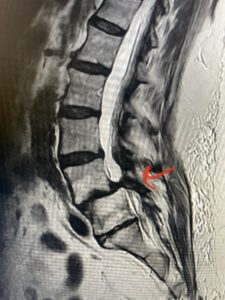

Fig 1: Sagittal T2-weighted lumbar MRI demonstrating grade 1-2 spondylolisthesis L4-5 with severe stenosis (red arrow)

This 73 year-old female had a long history of low back pain and left thigh pain and heaviness of her legs when she ambulated or did activities. She failed all means of conservative treatment including epidurals and PT. On exam she had mild weakness of her left quad but otherwise was intact. Lumbar MRI (Fig 1) revealed significant L4-5 lumbar stenosis and a grade 1-2 spondylolisthesis. Her main pathology was severe, thickened “knobs” of ligamentum forming at the posterior margin of the superior facet processes of L5 and lamina (Fig 2). The patient underwent a decompressive laminectomy of L4 as well as removal of the inferior processes of L5 to widely decompress bilaterally the L4 and L5 nerve roots. Intraoperatively, the descending L5 nerve roots were compressed severely by this severe thickened ligamentum in the subarticular recess. Because of the significant spondylolisthesis we augmented her decompression with fusion. She underwent an L4-5 posterolateral fusion with segmental instrumentation (Fig 3)). Postoperatively she had an uneventful course with relief of her leg pain.